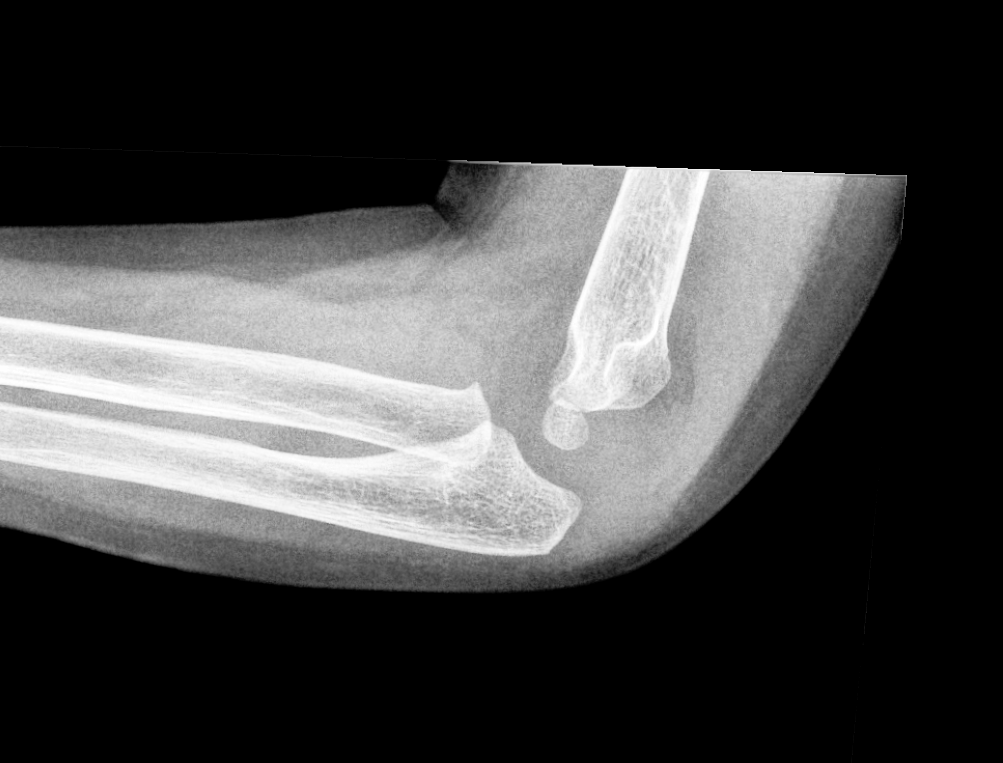

Info Images Findings Impression Reco/Acuity Case Images View Images / Launch Visage Case Notes History 2-month-old presents with decreased right arm movement, increased fussiness, and increased sleepiness for 2 days. Suspected non-accidental trauma. Exam Skeletal survey Prior Study none Dicom View Reference Material

Section 1 Submit Findings CB1550 Findings Skeletal Survey - Technique Check Skull AP/Lat Yes No Cervical and Thoracolumbar spine Yes No Chest X-Ray Yes No Ribs – Left/Right Oblique Yes No Abdominal X-Ray Yes No Pelvis with both hips Yes No Bilateral Humerus, Forearm, Hand Yes No Bilateral Femur, Tibia/fibula, feet Yes No Any additional lateral views of the extremities Yes No The exam is over or under penetrated. Yes No The exam may or may not be limited by overlying structures or soft tissues, body habitus, patient positioning, support devices, or motion. Yes No The area of concern is indicated by the patient, technologist, or care provider. Yes No The area of concern is included on the exam. Yes No Soft Tissues There is soft tissue swelling, indistinctness of fat/muscle planes, gas, or laceration in the area of clinical concern. Yes No There is an effusion, fat pad displacement, or fat fluid level. Yes No There is a radiodense or lucent foreign body. Yes No There are other densities, calcifications, post-surgical changes, or support devices in the soft tissues. Yes No Any support lines/tubes. Yes No Bone There is a break or interruption of the continuity of the cortical or cancellous bone. Yes No There is overriding of the trabeculae with apparent sclerosis. Yes No There is displacement of a fracture fragment. Yes No There is bowing of the bone in addition to the fracture at the apex of the bowed bone concerning for the greenstick. Yes No There is a spiral fracture of the leg concerning for toddler’s fracture. Yes No There is abnormal angulation or bulging of the cortical surface relative to the normal cortex which could be from a buckle or torus fracture. Yes No There is a displaced fragment which may be from avulsion by a tendon, ligament, or joint capsule or from a comminuted or other fracture. Yes No The stress trabeculae or other trabeculae of the cancellous bone are interrupted or otherwise abnormal. Yes No There is subperiosteal or endosteal reaction which could indicate a healing or subacute fracture or other abnormality. Yes No There is hard/soft callus formation. Yes No There is remodeling of the bone. Yes No There is a corner fracture or metaphyseal lesion that could be from nonaccidental trauma. Yes No There are multiple fractures of different ages. Yes No There are vertebral body/spinous process fractures. Yes No There are rib fractures. Location - posterior or lateral. Yes No There is scapular/sternal fracture. Yes No There are fractures of the digits. Yes No There are wormian bones. Yes No There are intrasutural bones. Yes No There is metaphyseal abnormality (lucencies, increased density, erosion) which may be from something other than injury such as stress, metabolic disease (e.g. rickets with loss or distortion of the zone of the provisional calcification), neoplasm (e.g. leukemia), heavy metals, inflammation, or infection. Yes No There are metaphyseal spurs. Yes No There are bony deformities involving multiple bones. Yes No The bones are gracile. Yes No There are non-healing fractures. Yes No There is/are focal or multifocal lytic/lucent, blastic/sclerotic or mixed density lesion(s) or other abnormality. Yes No Overall bone density is increased or decreased with or without thinning or thickening of the cortical or cancellous bone. Yes No Growth plates, ossification centers, apophyses The growth plate(s) is/are abnormal. Yes No There is widening of the physis from a fracture with or without displacement of the epiphysis (Salter-Harris I). Yes No There is a fracture through the physis which then extends into the metaphysis with or without angulation or displacement (S-H II). Yes No There is a fracture through the physis which then extends into the epiphysis and is intra-articular, with or without angulation or displacement (S-H III). Yes No There is a fracture through the metaphysis, physis, and epiphysis which extends into the joint space with or without angulation or displacement (S-H IV). Yes No There is narrowing of the physis from a compression fracture (S-H V). Yes No The apophysis, epicondyle, secondary ossification center, or accessory ossicle is displaced or otherwise abnormal. Yes No The ossification centers are underdeveloped. Yes No Joints and alignment There is an effusion, fat pad displacement, or fat fluid level. Yes No The epiphysis or subchondral bone is fractured, interrupted, flattened, compressed, impacted, displaced, or otherwise abnormal. Yes No There is an intra-articular loose body or chondrocalcinosis. Yes No The joint is widened, narrowed, dislocated, malaligned, or incongruent. Yes No There is pseudoarthrosis. Yes No Other findings There are developmental changes or other anatomic variants or other existing conditions that may or may not be contributing to symptoms which can or should be further evaluated non-emergently or are otherwise incidental. Yes No The remainder of the exam is abnormal for age. Yes No The lungs show focal airspace opacity. Yes No There is pneumothorax. Yes No There is organomegaly. Yes No There is intra-abdominal calcification. Yes No There is displacement of the bowel loops. Yes No There is free intraperitoneal air. Yes No The bowel loops are dilated/obstructed. Yes No There is paraspinal soft tissue abnormality. Yes No